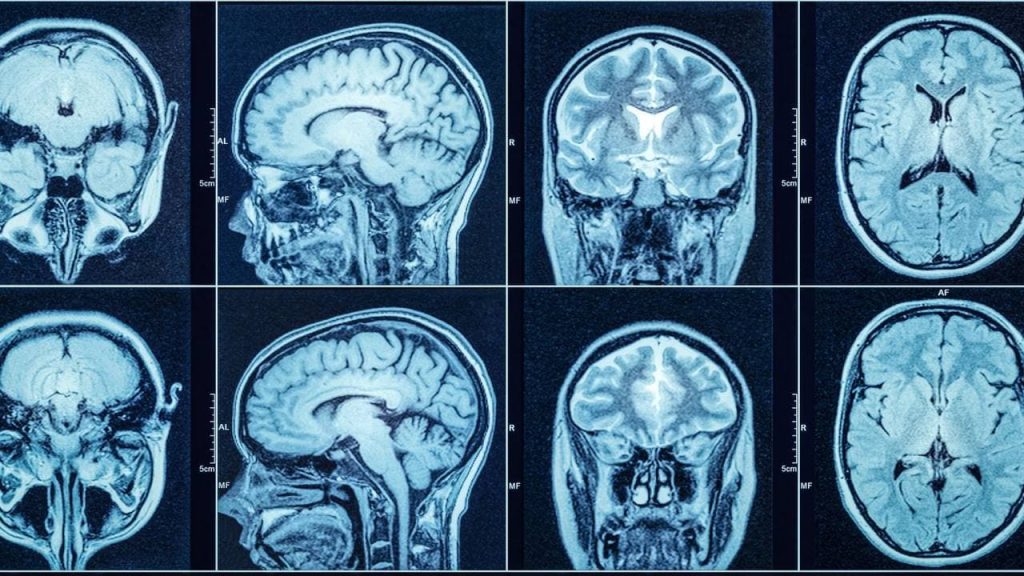

Компьютерная томография головы — это высокоточный метод визуализации, при котором выполняется серия послойных рентгеновских снимков головы с последующей компьютерной обработкой. Полученные данные формируют трёхмерное изображение тканей мозга, костей черепа и других структур, позволяя детально оценить их состояние в любой проекции.

КТ мозга четко показывает ткани различной плотности (так определяются контуры различных частей мозга) и биологической активности (так определяются более активные клетки опухолей и метастазов в мозг). Благодаря своей информативности этот вид диагностики решает такие важнейшие задачи: